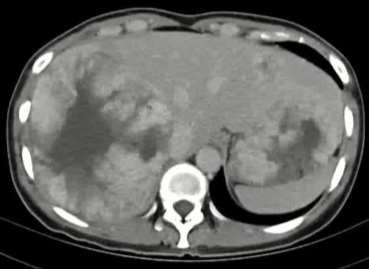

栓塞材料的可及性(例如病灶栓塞材料的可到达性)accessability (e.g. reachability of the nidus) 栓塞的预期深度intended deepness of embolization 如果需要让栓塞填满最后1mm 预期效果(例如:门静脉栓塞的炎症)intended effect (e.g. inflammation in PVE) 凝血状态(达到止血效果所需的时间)coagulation state (duration until hemostasis) 并发症(过敏、心律不齐、肺动脉高压、肝纤维化等)comorbidities (allergies, arrythmia, pulmonary hypertension, lung fibrosis etc.) 处于危险中的结构(包括下游部分-downstream和反流部分) structures at risk (downstream & backwash) 靶病变定位(浅层与深层) target lesion localization (superficial vs. deep) 不会选择一些会引起炎症的东西,因为那会病人来说真的很痛苦浅层病变 栓塞所需的速度(例如:危及生命的出血情况)required speed of embolization (e.g. life threatening hemorraghe) 院外专业人员(DSA技术人员和介入放射科医生)local expertise (technicians & IR's) 可用性与定价 availabilty & pricing Patient assessment for the choice of the ideal liquid emboli 影像学 62岁 男性